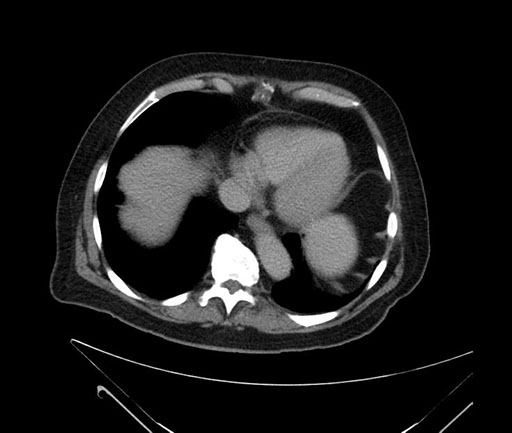

Imaging Analysis

Look through the patient's CT scan to identify any areas of concern for the necessary procedure.

Based on your CT findings, which issue(s) would give reason for "planned slowing down moment(s)" in this case?